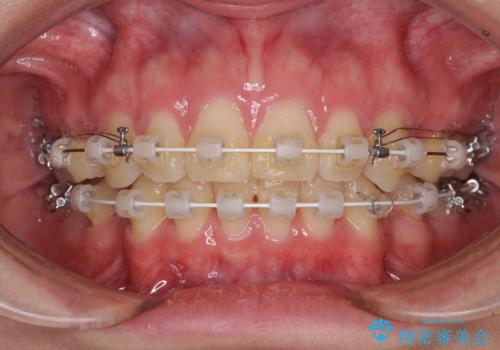

上顎前突 目立たないワイヤー装置での抜歯矯正

- 審美装置

- 口元の突出感改善を希望して来院された患者様です。

口元を積極的に引っ込めるために、上下左右の小臼歯計4本を抜歯することとしました。

咬み合わせが深いため、咬み合わせの高さを向上させながら口元を下げることとしました。

左右ともに下顎に対して上顎歯列が前方位にある上顎前突であったので、上顎歯列全体を後方に移動させることで上下咬み合わせを改善し、その上で抜歯矯正により口元の突出感を改善させていきました。